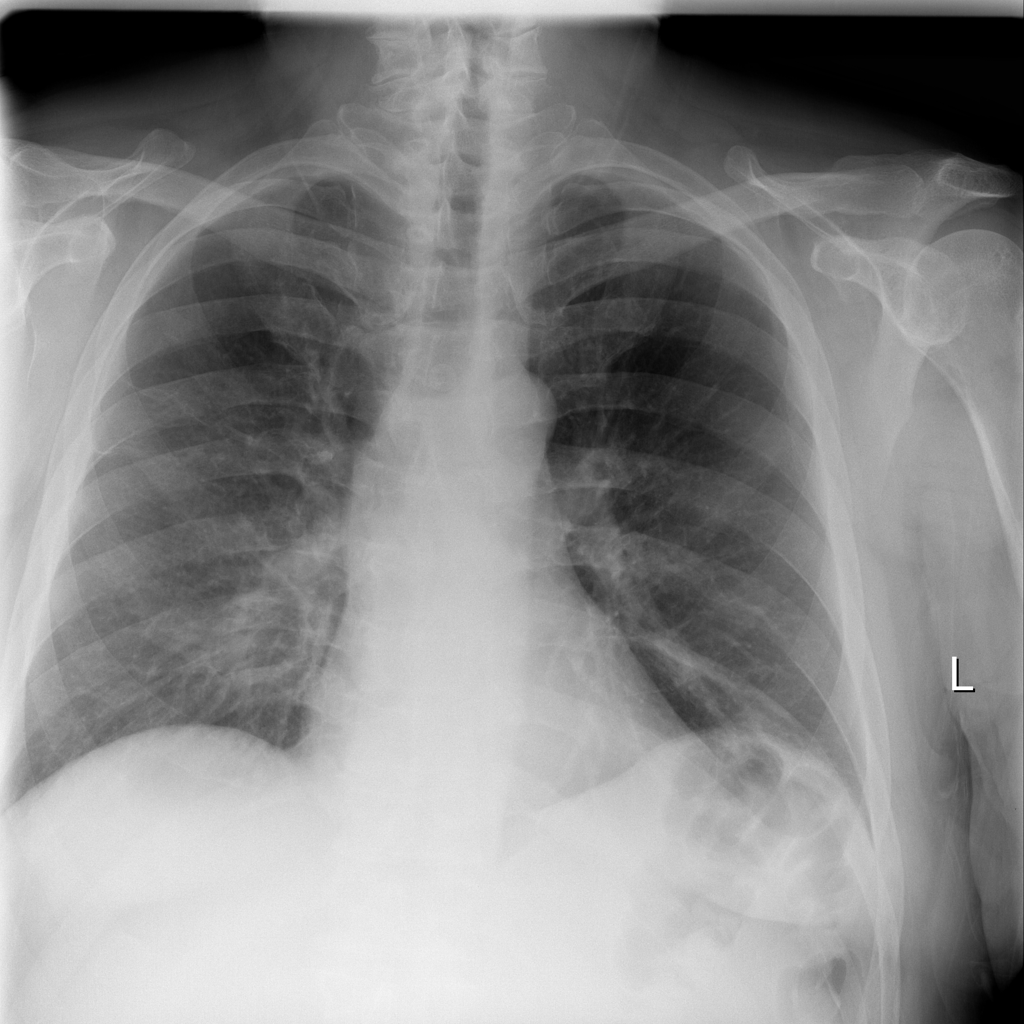

PAT-B3C3 · IMG-001Pneumonia

PAT-B3C3 · IMG-001

PA